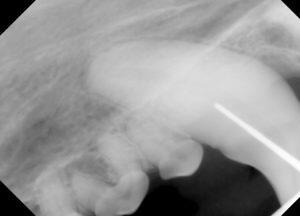

2.レントゲンでは、歯周炎による重度の骨吸収像が認められ、

3.骨の浸潤や破壊は認められません。